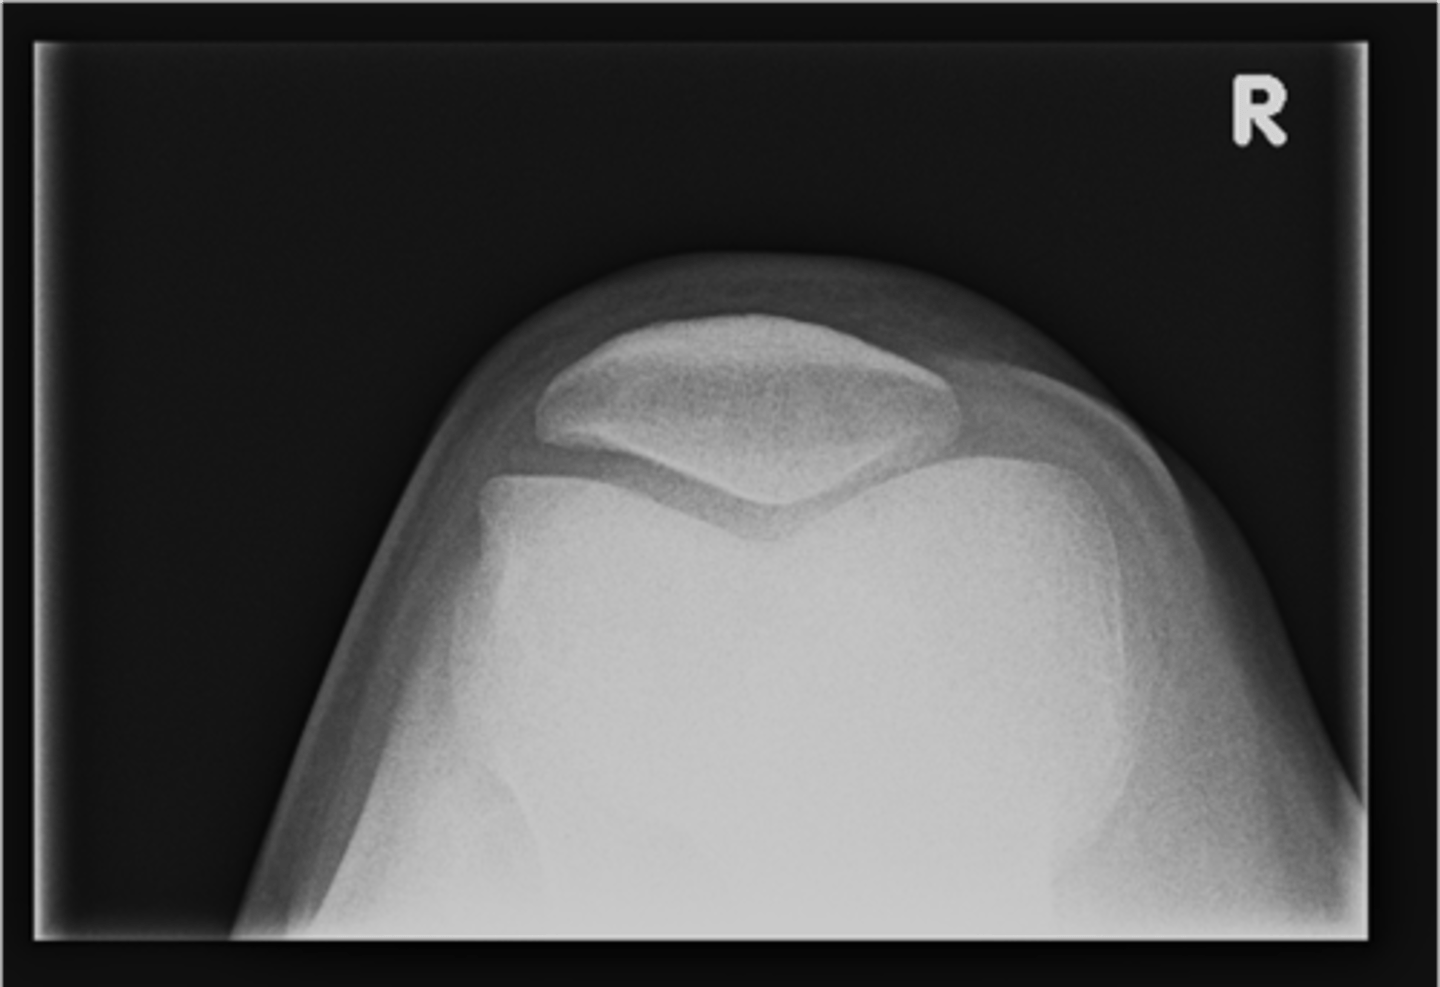

No - growth plate in a child

Broken?

<p>Broken?</p>

21

New cards

AP hip

View on left?

<p>View on left?</p>

Frog-leg hip

View on right?

<p>View on right?</p>